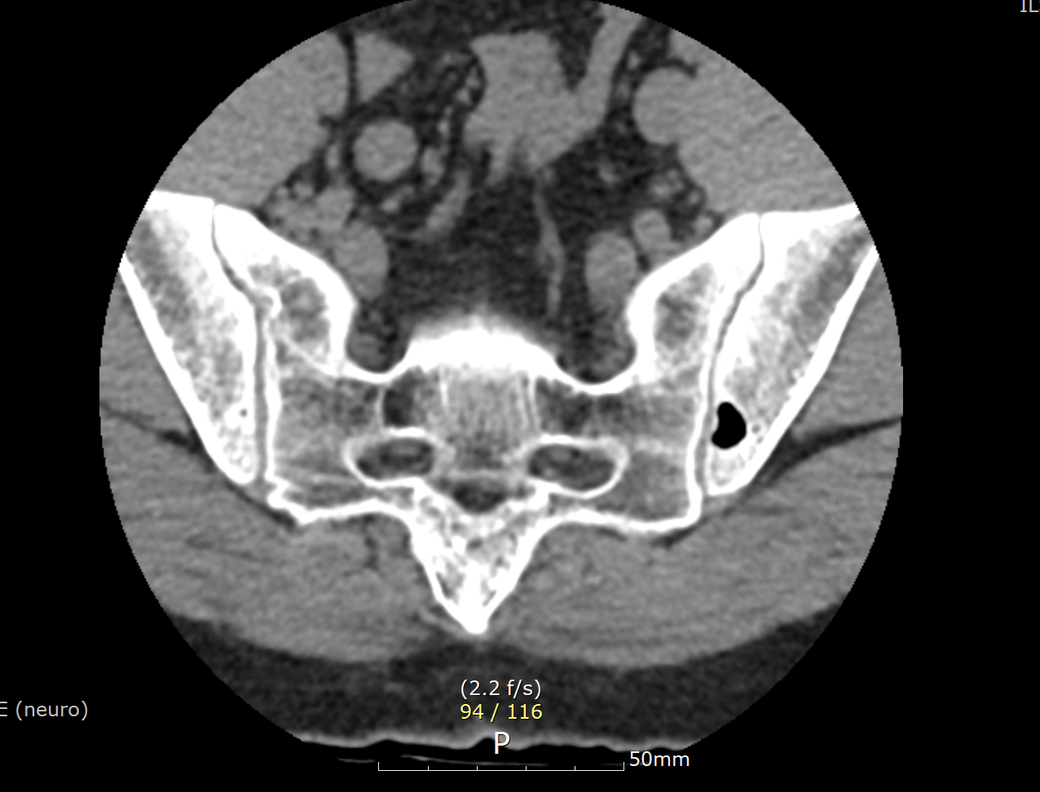

ct상 뼈에 구멍이 나보이는데 뭘까요?

현재 2달 조금 넘게 허리통증으로 외래진료 받는중인데 차도가 없어 ct를 촬영했는데 우연하게

골반뼈에 구멍 같은걸 발견했어요. 심각한 문제일까요?

• CT 소견만 놓고 정확한 상태를 알기는 어렵지만 골반 뼈 부위에 비어있는 구멍이 있는 것으로 보이며 이외에 특이 소견은 보이지 않습니다. 허리 통증과 무관해 보이며 당장 큰 문제가 있다고 보기에는 애매합니다.